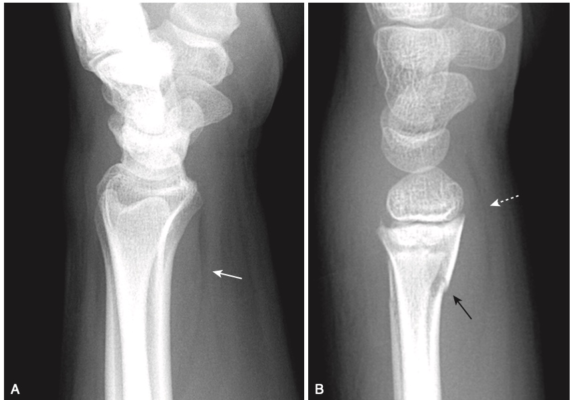

- Gãy xương có thể không được chẩn đoán được cho đến khi xảy ra quá trình tạo xương mới ở màng xương hoặc có sự xuất hiện của một vùng xơ cứng mỏng, đậm đặc trong khoang tủy trong trường hợp gãy xương do mỏi đang lành ở xương xốp (Hình 3).

Gãy bánh bơ (Buckle fractures) xương quay và/hoặc xương trụ

- Thường gặp ở trẻ em

- Tìm kiếm sự gập góc đột ngột, nhọn của vỏ xương, đặc biệt là gần cổ tay (xem Hình 1, bài Chẩn đoán gãy xương). Đây là những gãy xương do va đập và thường lành nhanh chóng mà không bị biến dạng.